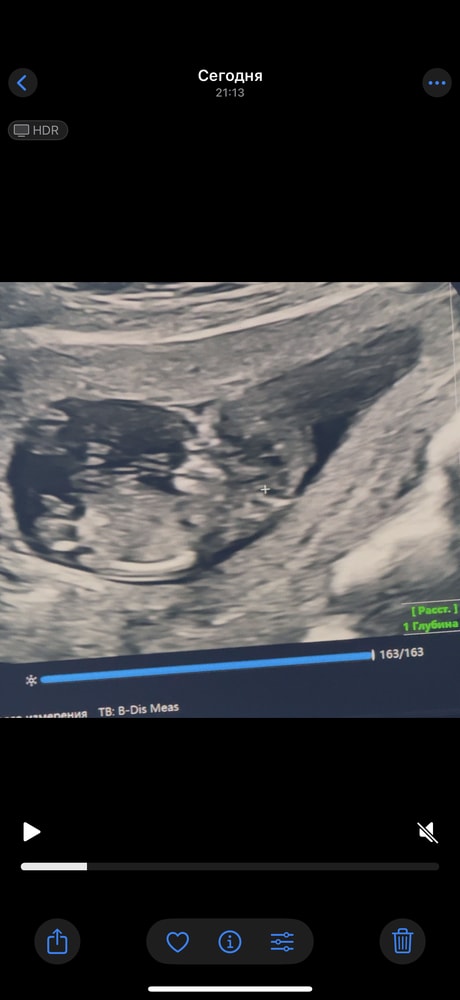

Половой орган мальчика? Не пуповина ли?))

это правда половой орган мальчика ?)

не пуповина или что-то другое?

Но сама узистка сказала и вот показала что мальчик скорее всего …Но 100 % не дала

Да, нам вчера доктор тоже показал этот бугорок, прямо точно как на второй фотке у вас, сказал это 100% мальчик. А пуповина она же на животе. Ее совсем по другому видно.